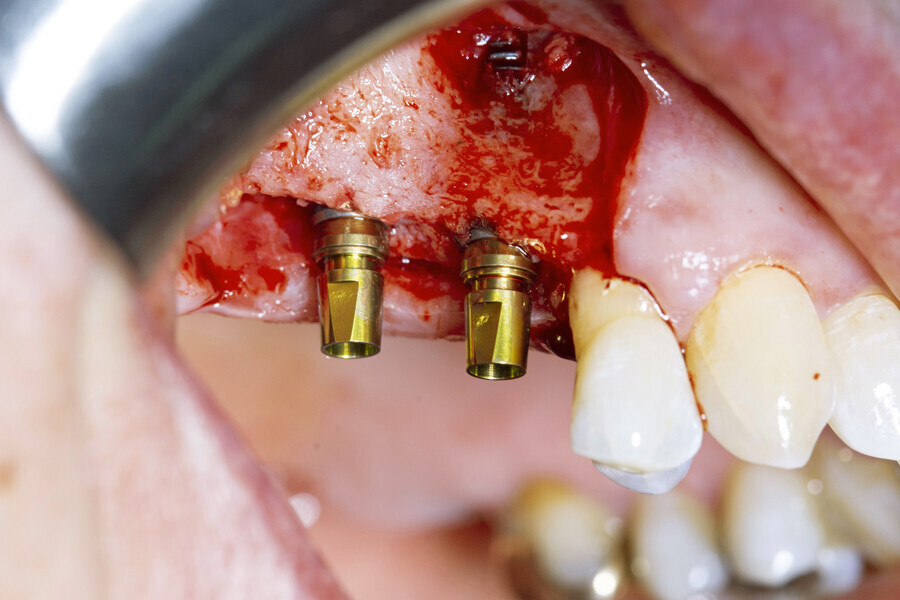

A full-thickness envelope flap was raised with relieving incisions, and the initial small round guide drill was used to mark the implant position. The site was enlarged with OmniTaper drills of different diameters, following the recommended drilling protocol. The initial osteotomy preparation was performed with a 2mm diameter OmniTaper drill at no more than 1,500 rpm and with copious external irrigation with saline according to the surgical protocol (Fig. 3). An OmniTaper EV 3.8 × 11.0 mm implant was placed in position #15 using the TempBase driver (Fig. 4). Both OmniTaper EV implants placed with the help of the preassembled TempBase abutments nicely aligned in positions #15 and 16 (Fig. 5).

Fig. 3: Full-thickness envelope ap and direction indicators after initial preparation with the 2 mm diameter OmniTaper drill.

Fig. 4: Placement of the OmniTaper EV implant in position #15 using the TempBase driver.

Fig. 5: Both OmniTaper EV implants placed with the help of the preassembled TempBase abutments nicely aligned in positions #15 and 16. Implant–abutment connection size of medium indicated in yellow.